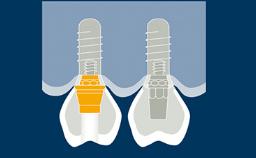

种植体支持式固定义齿旨在为缺失牙齿提供修复义齿,从而能承担相应的功能性需求,并且准确模拟缺失牙单位的美学效果。理想情况下,修复体应与周围牙齿难以分辨。为此,临床医生必须选择最佳的可用材料,来应对临床病情的种种挑战。本模块将讨论可用于制作种植体支持式固定义齿的牙科材料,以及为每个病例选择最合适的材料的基本原则。